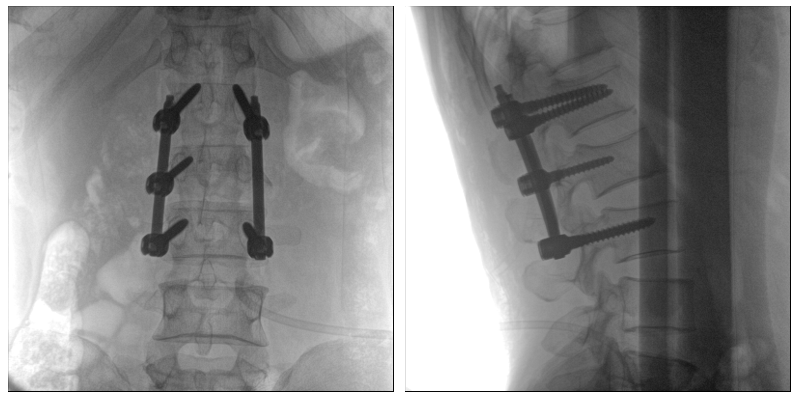

術中二維影像

從圖中可以看到二維影像能夠提供目標區域在某一個平面的重疊影像,雖然因為人體不同組織的密度差異,使得圖像具有較為豐富的信息量,但組織間的相互重疊還是會出現,諸如空間位置等眾多信息在影像中遺失或不可辨認的情況,影響了醫生對信息的收集與應用。

術中三維影像

而三維影像的MPR圖像組可以通過不同平面的切分,使成像區內更豐富的信息得以呈現。尤其是二維影像無法涉及的橫斷面,提供了另一個空間維度的信息量。